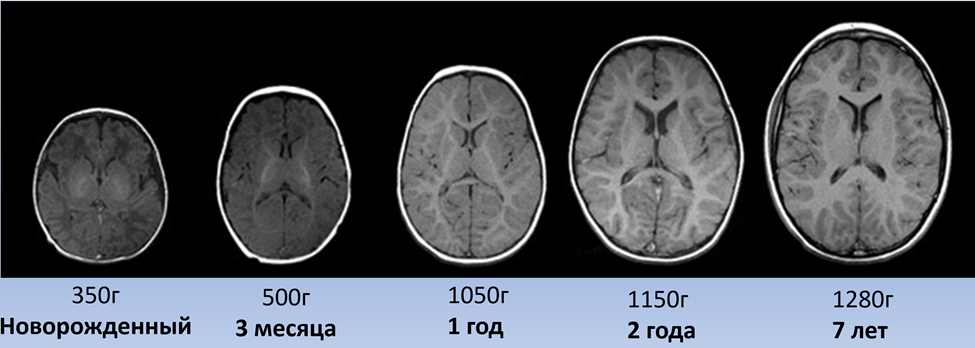

Масса мозга при рождении составляет в среднем около 350грамм. Именно такой размер мозга сформировался эволюционно как баланс между размером и возможностями организма женщины к успешному разрешению родов. В тоже время мозг человека при рождении совершенно не развит, хотя и содержит уже практически все нейроны, которые будут и во взрослом возрасте.

Масса мозга быстро увеличивается до 7 лет, достигая средней величины 1270 грамм. Особенно быстро это происходит в первый год. Вес мозга утраивается, достигая величины 1050грамм. (рис. 1)